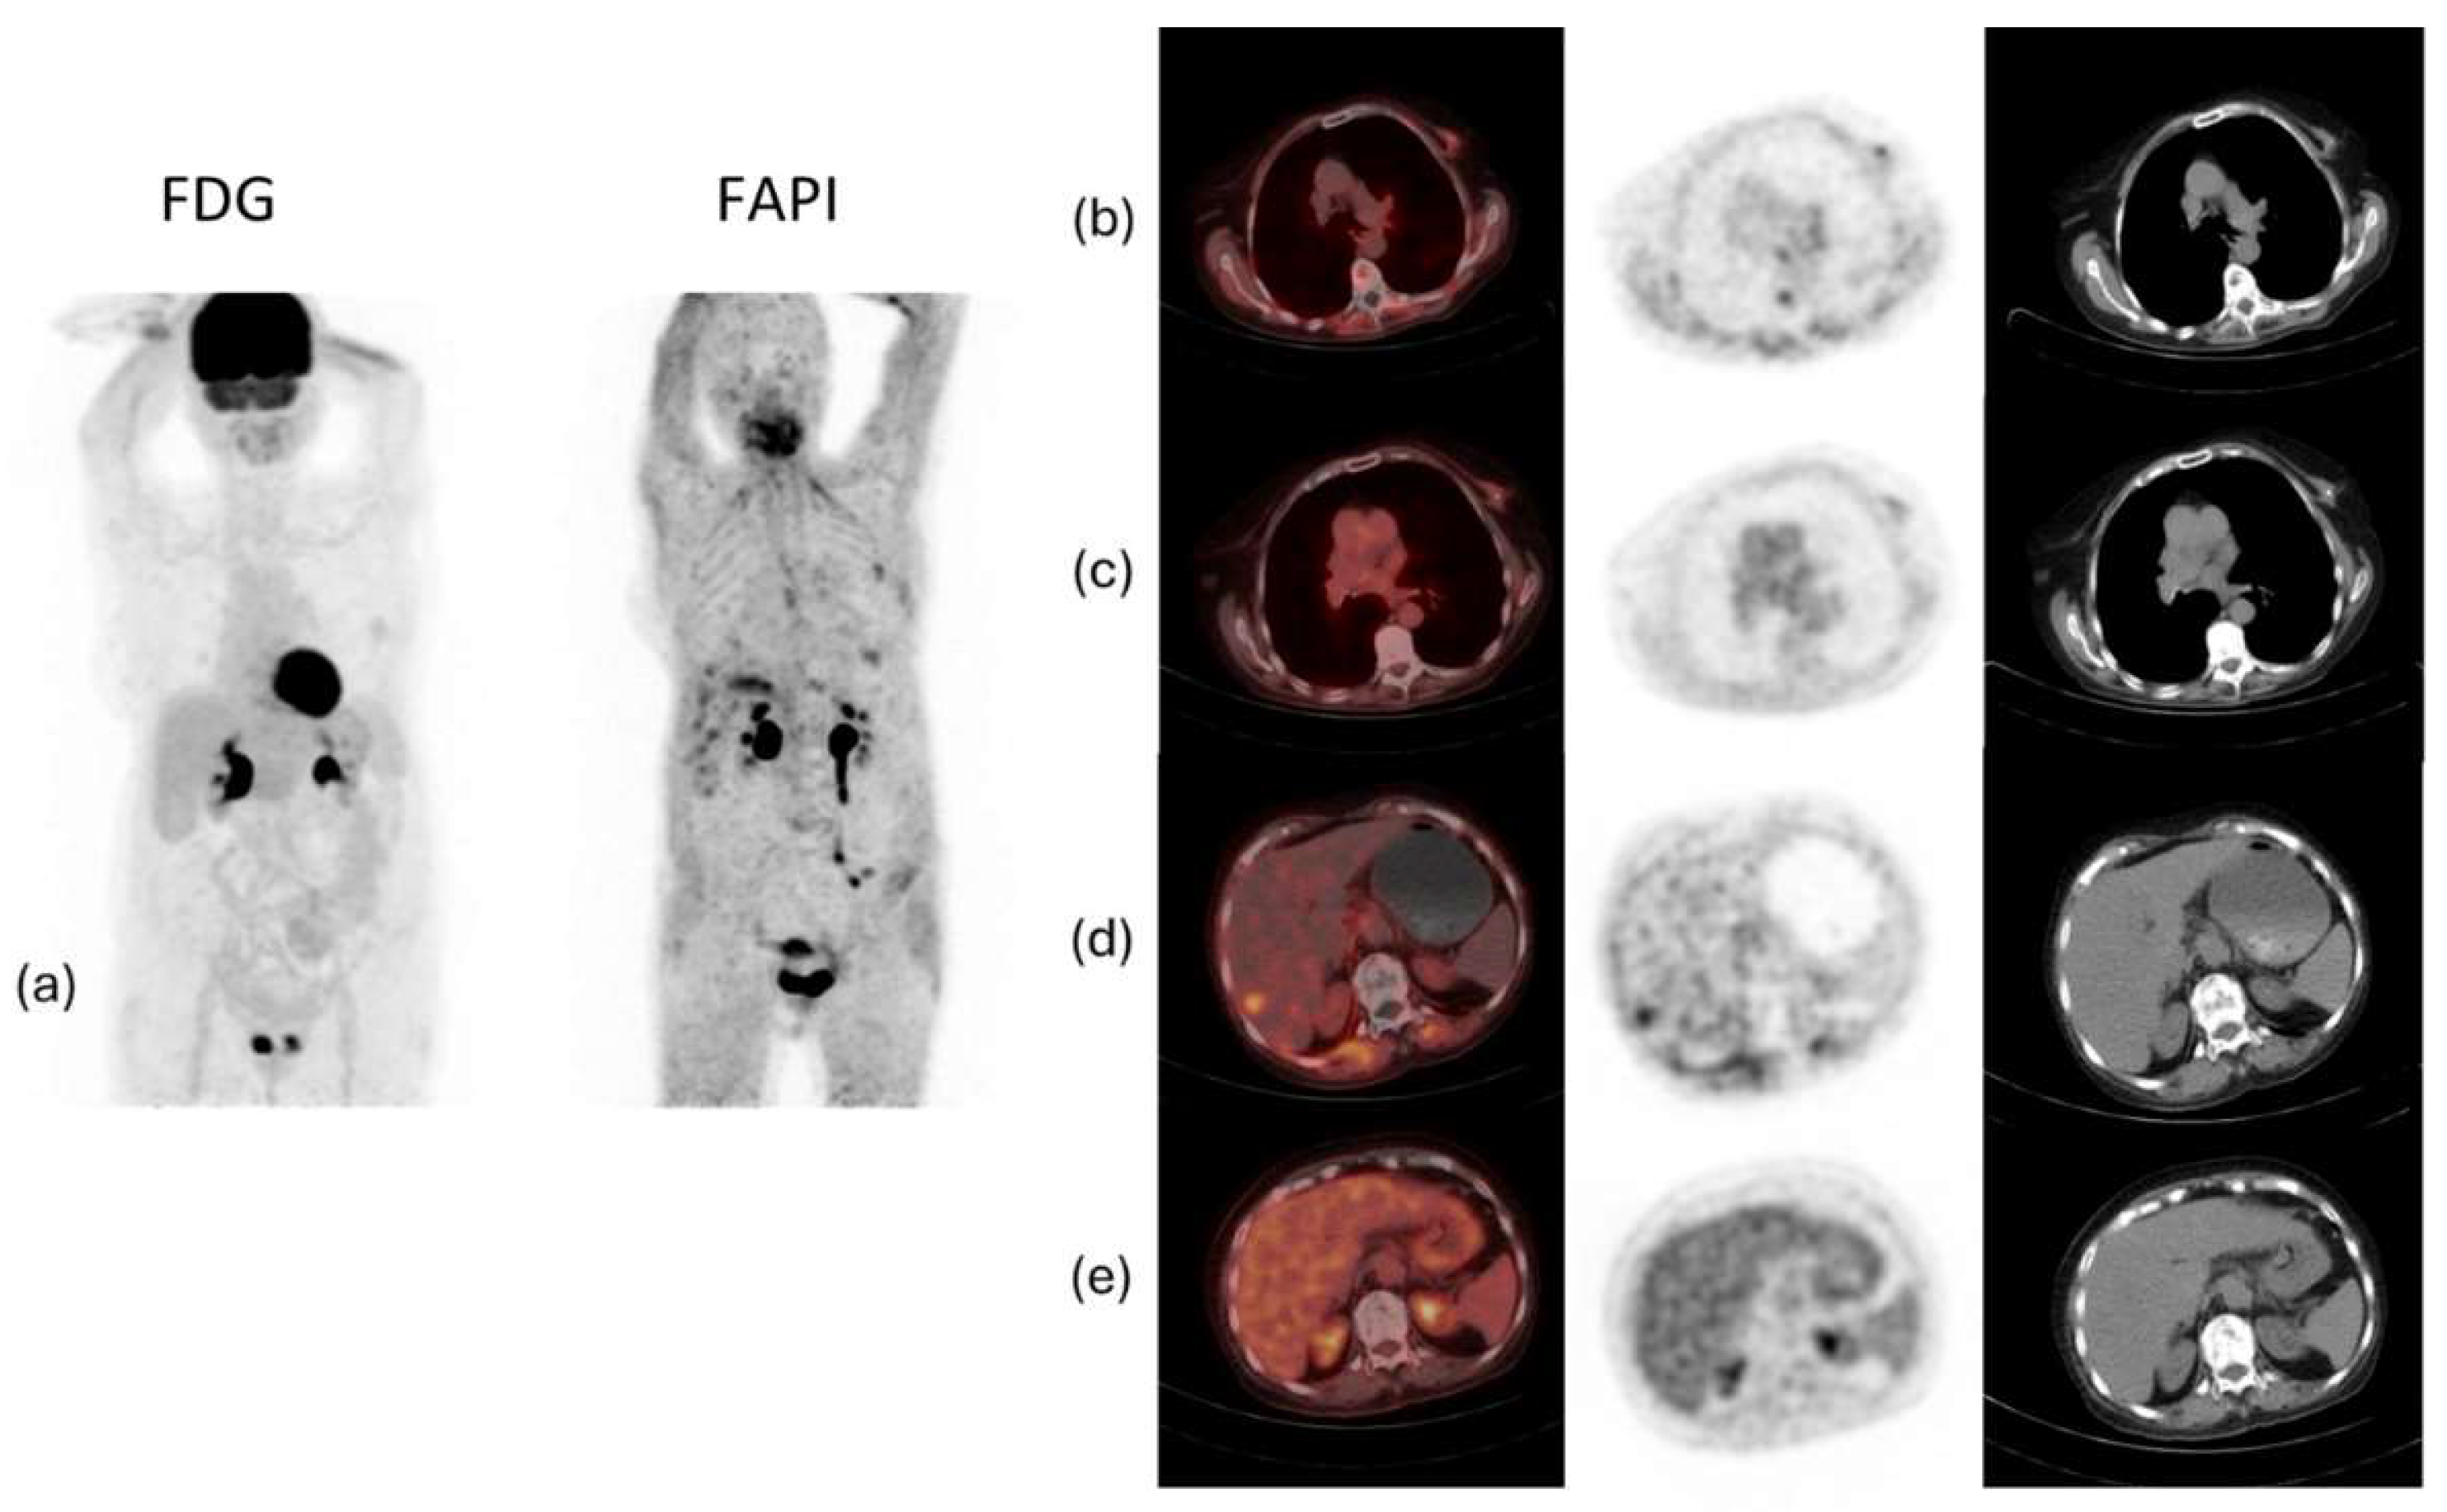

When comparing 68Ga-FAPI to 18F-FDG in diagnosing breast cancer, studies have shown that 68Ga-FAPI had a higher overall tumor uptake in breast cancer and a higher metastatic detection rate than 18F-FDG specifically when metastasis was in the bone and peritoneum [60,61,62,63]. One of the disadvantages of 18F-FDG is its low specificity since benign conditions such as infection, fibroadenoma, ductal adenoma, inflammatory granulomatous mastitis, and fibrocystic changes are also FDG-avid [33]. In such cases, using 68Ga-FAPI might be a better choice in breast cancer staging since it is more specific and has a decreased uptake in the brain, liver, and oral mucosa [64].

Studies have also demonstrated that 68Ga-FAPI PET/CT is superior to 18F-FDG PET/CT in ILC by showing higher tumoral activity and tumor-to-background uptake ratios, and by detecting more primary tumors, axillary lymph node metastases, and additional foci, including multicentric cancer. Furthermore, 68Ga-FAPI PET/CT detected more bone and liver metastases, and a positive association was made between the peritumoral lymphocyte ratio and 68Ga-FAPI PET/CT-to-18F-FDG PET/CT uptake ratios [38]. 68Ga-FAPI PET/CT showed increased effectiveness in detecting lesions in the breast, lymph nodes, lung, liver, and bone [65,66]. Moreover, compared to CT alone, 68Ga-FAPI PET/CT detected more lesions, especially in infiltrative soft tissue and serosal locations [65]. However, larger cohorts are needed to assess these findings further. Figure 5 shows an example of a case of metastatic ILC with comparison between 18F-FDG PET/CT and 68Ga-FAPI PET/CT, demonstrating that the latter was better able to detect the primary malignancy as well as the metastatic lesions.